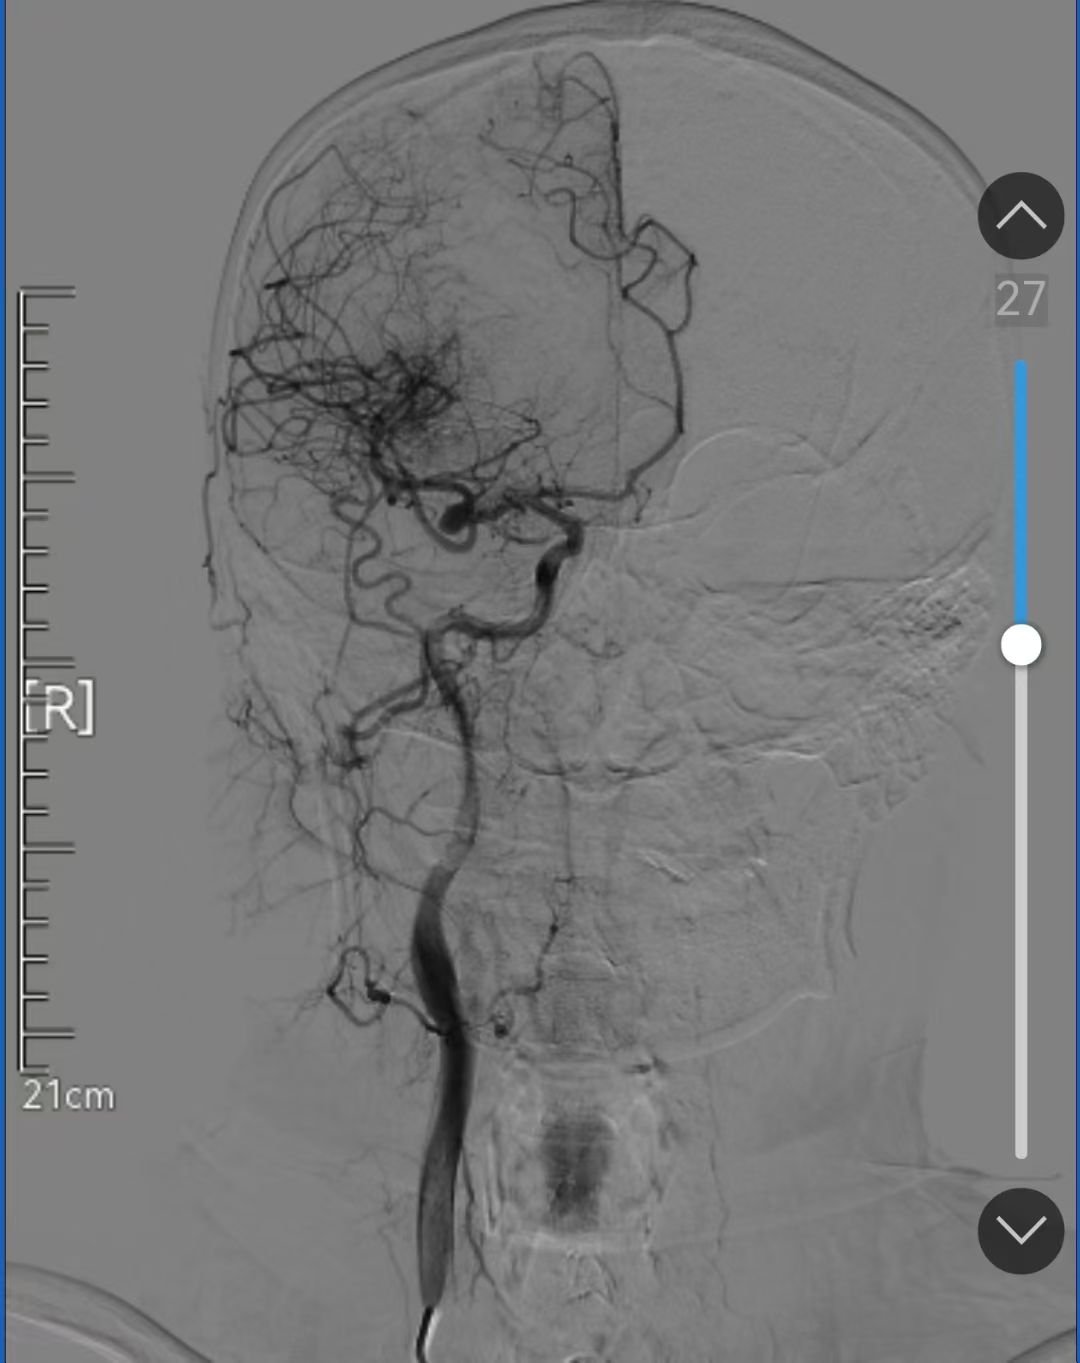

面对这样的情况,团队陷入了沉思。如果选择分期手术,佟先生将面临二次开颅的风险;若强行同期切除,术中大出血可能出现致命危险。经过严谨的术前讨论,团队最终决定采用“双管齐下”策略,先行数字减影血管造影(以下简称DSA)下脑膜瘤供血动脉栓塞,精准阻断肿瘤“输血管”,然后再行脑膜瘤切除并同期夹闭动脉瘤。

术前DSA造影证实脑膜瘤血供丰富

与颅内动脉瘤关系密切